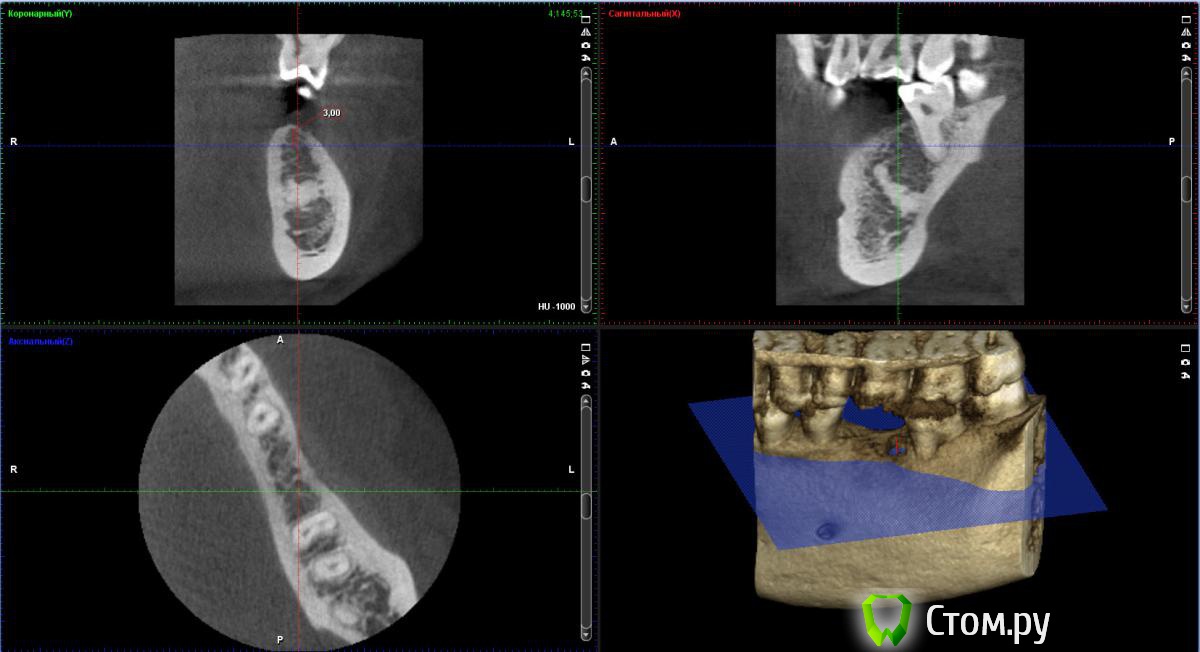

bobrdobr Опубликовано 17 февраля, 2014 Автор Поделиться Опубликовано 17 февраля, 2014 Добрый всем день. Сделал КТ. Снимок выложил на Яндекс.Дискhttp://yadi.sk/d/-CHDNu-nJ45Wy Посмотрите пожалуйста. Вопрос прежний: нужна ли костная пластика в каком-то виде перед установкой винтового импланта? Ссылка на комментарий

bobrdobr Опубликовано 17 февраля, 2014 Автор Поделиться Опубликовано 17 февраля, 2014 Хорошо. Так подойдет? Ссылка на комментарий

Bier Опубликовано 17 февраля, 2014 Поделиться Опубликовано 17 февраля, 2014 судя по фото, скорее всего нужна. От КТ нужен срез горизонтальной плоскости - вид сверху на костный гребень, на 1 мм ниже его вершины. Ссылка на комментарий

bobrdobr Опубликовано 18 февраля, 2014 Автор Поделиться Опубликовано 18 февраля, 2014 (изменено) Имплант был предложен Semados 4,1*11,5 без костной пластики. судя по фото, скорее всего нужна. От КТ нужен срез горизонтальной плоскости - вид сверху на костный гребень, на 1 мм ниже его вершины. Сейчас попробую. Прикладываю 4 снимка: на уровне гребня (как мне кажется) и на 1,2,3 и мм. ниже. Изменено 18 февраля, 2014 пользователем bobrdobr Ссылка на комментарий